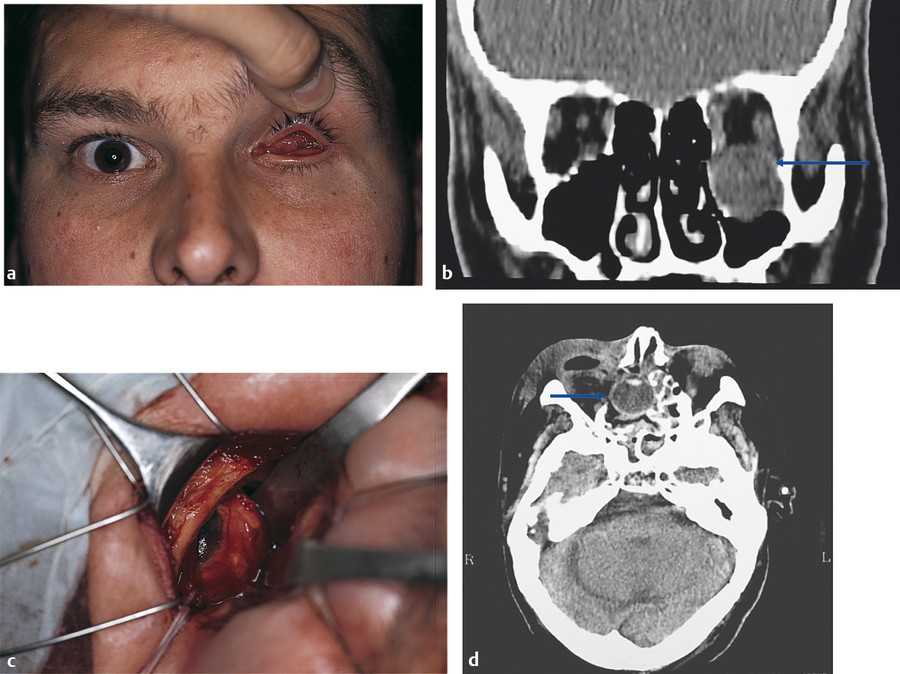

Enophthalmos is produced by an enlarged orbital volume and varies from insignificant to cosmetically disfiguring depending on the degree of orbital bony expansion. Fat atrophy usually contributes little if anything to the enophthalmos. Enophthalmos may be masked by orbital hematoma, edema, or air, which may even cause proptosis in the first few days after trauma. Proptosis, however, may be associated with a “blowin” fracture if the fragmented bones of the orbital floor are displaced into the orbit. This is more common in the context of fractures involving the roof of the orbit. Enophthalmos is always significant in the presence of combined fractures of the orbital floor and medial orbital wall. Hypoglobus is seen in the presence of extensive orbital floor blowout fractures. In some patients, the maxillary antrum extends laterally for some distance beyond the infraorbital neurovascular bundle, with the ensuing orbital floor defect occupying almost the whole orbital floor. Very rarely, the globe may come to lie within the maxillary antrum or even within the ethmoid sinus (Fig. 26‑3).

Enophthalmos results in a decreased support of the upper eyelid, which in turn leads to a secondary pseudoptosis and an upper eyelid sulcus deformity (Fig. 26‑4).